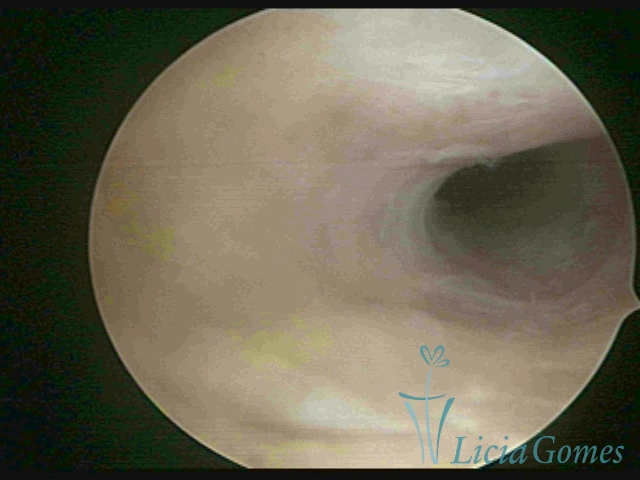

Terceira porção ou porção superior

Apresenta a mucosa com a superfície lisa e pouco vascularizada até a altura do orifício interno